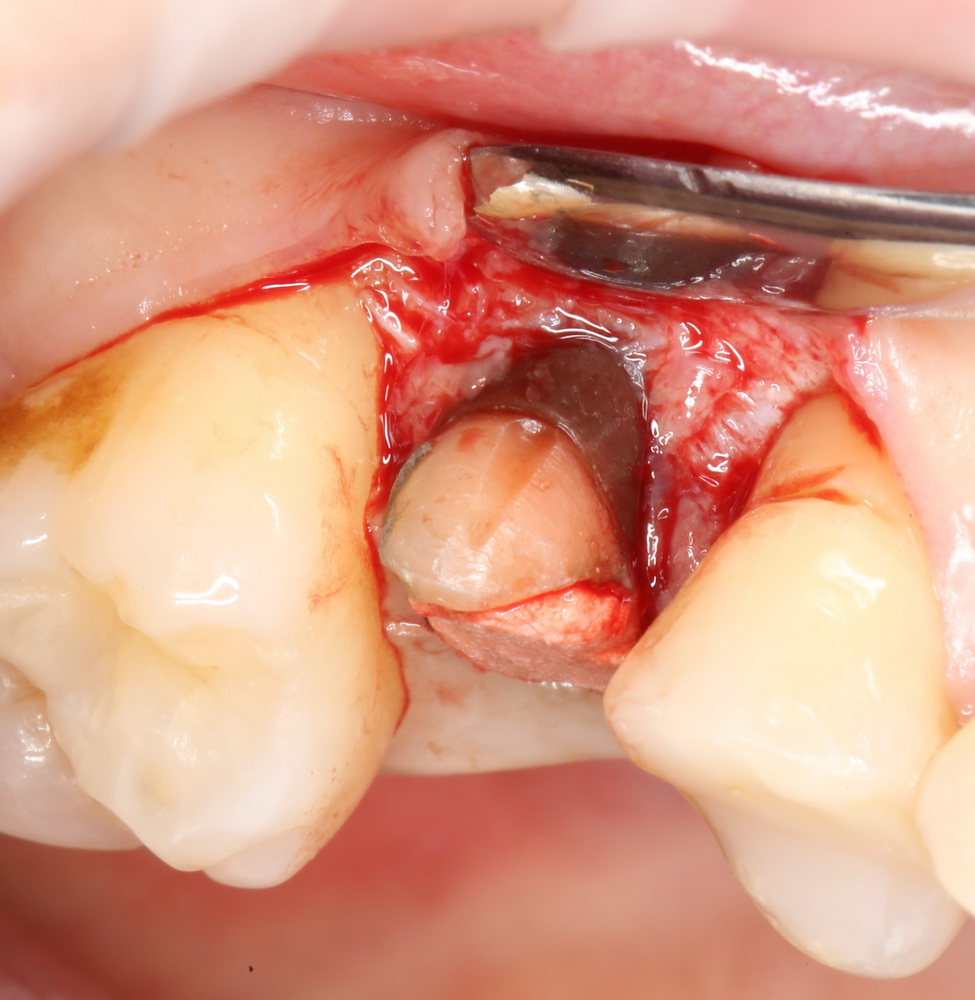

Биоматериал не нужно предварительно смачивать или увлажнять, он просто помещается в лунку в нужное положение:

Обратите внимание — у лунки отсутствует часть вестибулярной стенки. При использовании порошкообразного или гранулированного материала, мне пришлось бы отграничивать эту вестибулярную стенку с помощью барьерной мембраны. При использовании BioOss Collagen чаще всего этого не требуется.

Сам же материал достаточно гигроскопичен, чтобы быстро пропитаться кровью из лунки. Напомню, что именно жидкости являются транспортной средой в нашем организме, поэтому гидрофильные свойства во многом определяют способность биоматериала к интеграции:

Нет необходимости заполнять биоматериалом всю лунку. Не нужно заталкивать его в периапикальные области. Не забывайте о задаче — в первую очередь, нас интересует положение вестибулярной стенки, именно ее мы должны удержать на месте. Поэтому позиционируем наш графт, в основном, в верхней трети лунки: